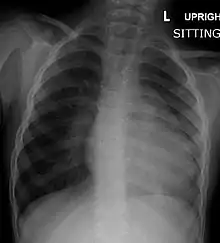

| Right ventricular hypertrophy | The right ventricle is more muscular than normal, causing a characteristic boot-shaped (coeur-en-sabot) appearance as seen by chest X-ray. Due to the misarrangement of the external ventricular septum, the right ventricular wall increases in size to deal with the increased obstruction to the right outflow tract. This feature is now generally agreed to be a secondary anomaly, as the level of hypertrophy tends to increase with age.[32] |

Before more sophisticated techniques became available, chest x-ray was the definitive method of diagnosis. The abnormal "coeur-en-sabot" (boot-like) appearance of a heart with tetralogy of Fallot is classically visible via chest x-ray, although most infants with tetralogy may not show this finding.[37] The boot like shape is due to the right ventricular hypertrophy present in TOF. Lung fields are often dark (absence of interstitial lung markings) due to decreased pulmonary blood flow.[15]:171–72